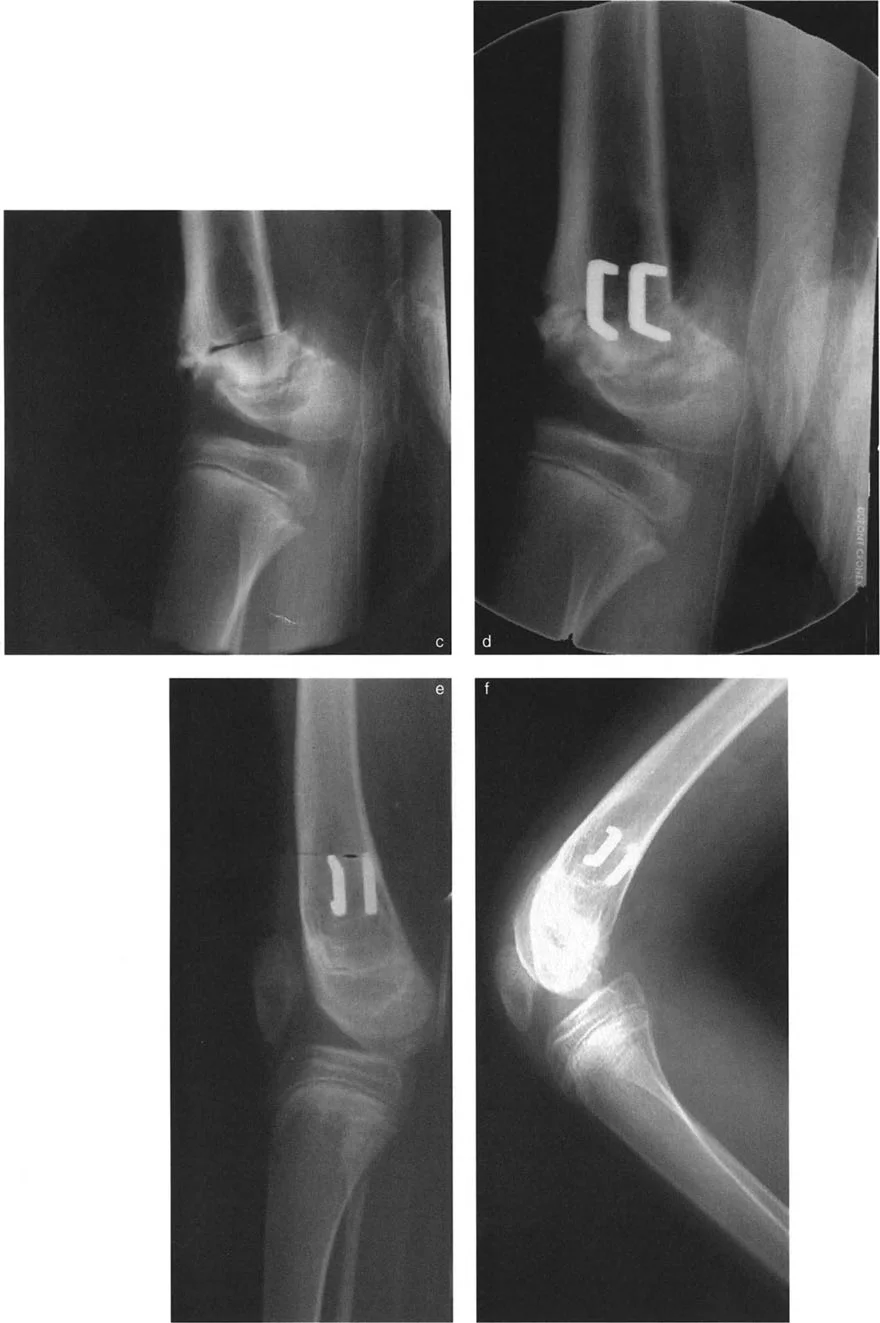

صورة توضح إزالة إسفين عظمي بزاوية 24° مع توجيه القاعدة خلفيًا. الأهم من ذلك، تبقى القشرة الأمامية سليمة لتعمل كمحور تصحيح الزاوية (ACA).